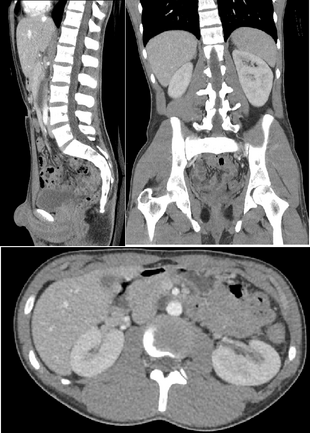

Detection and characterization of renal parenchymal masses is a frequent indication for CT. An initial noncontrast CT is important for detecting calcium or fat in a lesion, and to provide baseline attenuation of any renal masses. Following noncontrast scanning, intravenous contrast is injected and a corticomedullary phase is obtained at approximately 70 seconds (figure 7a, 7b). The corticomedullary phase is characterized by enhancement of the renal cortex as well as the renal vasculature. This phase is valuable in the evaluation of benign renal variants, lymphadenopathy and vasculature, however certain medullary renal masses may not be visible during this phase due to minimal enhancement of the medulla and collecting system. The parenchymal phase is obtained approximately 100–200 seconds after the injection of contrast material (figure 7c). Parenchymal phase imaging demonstrates continued enhancement of the cortex, enhancement of the medulla, and various levels of contrast material in the collecting system. The parenchymal phase is highly important for the detection and characterization of renal masses, parenchymal abnormalities, and the renal collecting system. This method of imaging does not evaluate for abnormalities of the collecting system.[citation needed]

FIGURE 7. Selected images from a renal mass specific protocol CT. Corticomedullary phase (axial 7a) demonstrates peripheral enhancement of the renal cortex with minimal opacification of the renal medulla. There is a large renal cell carcinoma in the left kidney (right in image) which can be differentiated from the normal renal parenchyma by the heterogeneous and differential enhancement. The renal artery and vein are opacified in this phase as well. The collecting system is not opacified (coronal reformat 7b). In the parenchymal phase, the renal cortex and the medulla are enhancing. The renal cell carcinoma in the left kidney is not as well defined when compared to the corticomedullary phase images, but is actually slightly more conspicuous. There is some contrast noted within the collecting system during this phase (7c).[citation needed]